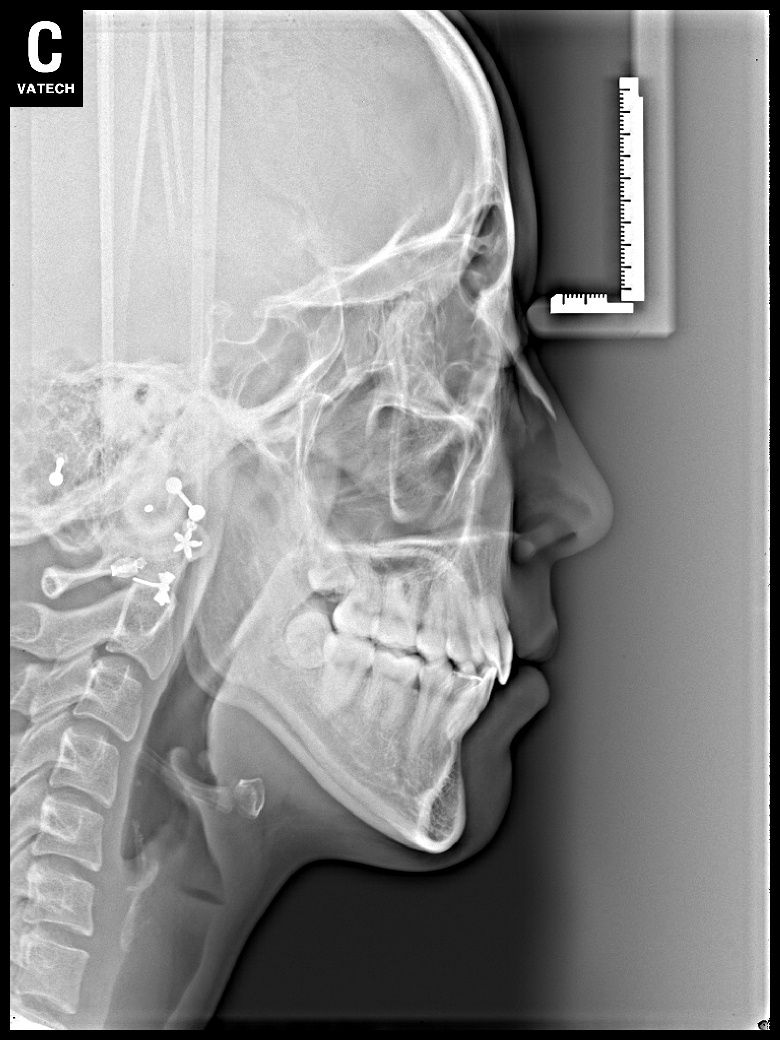

치료 전 사진입니다.